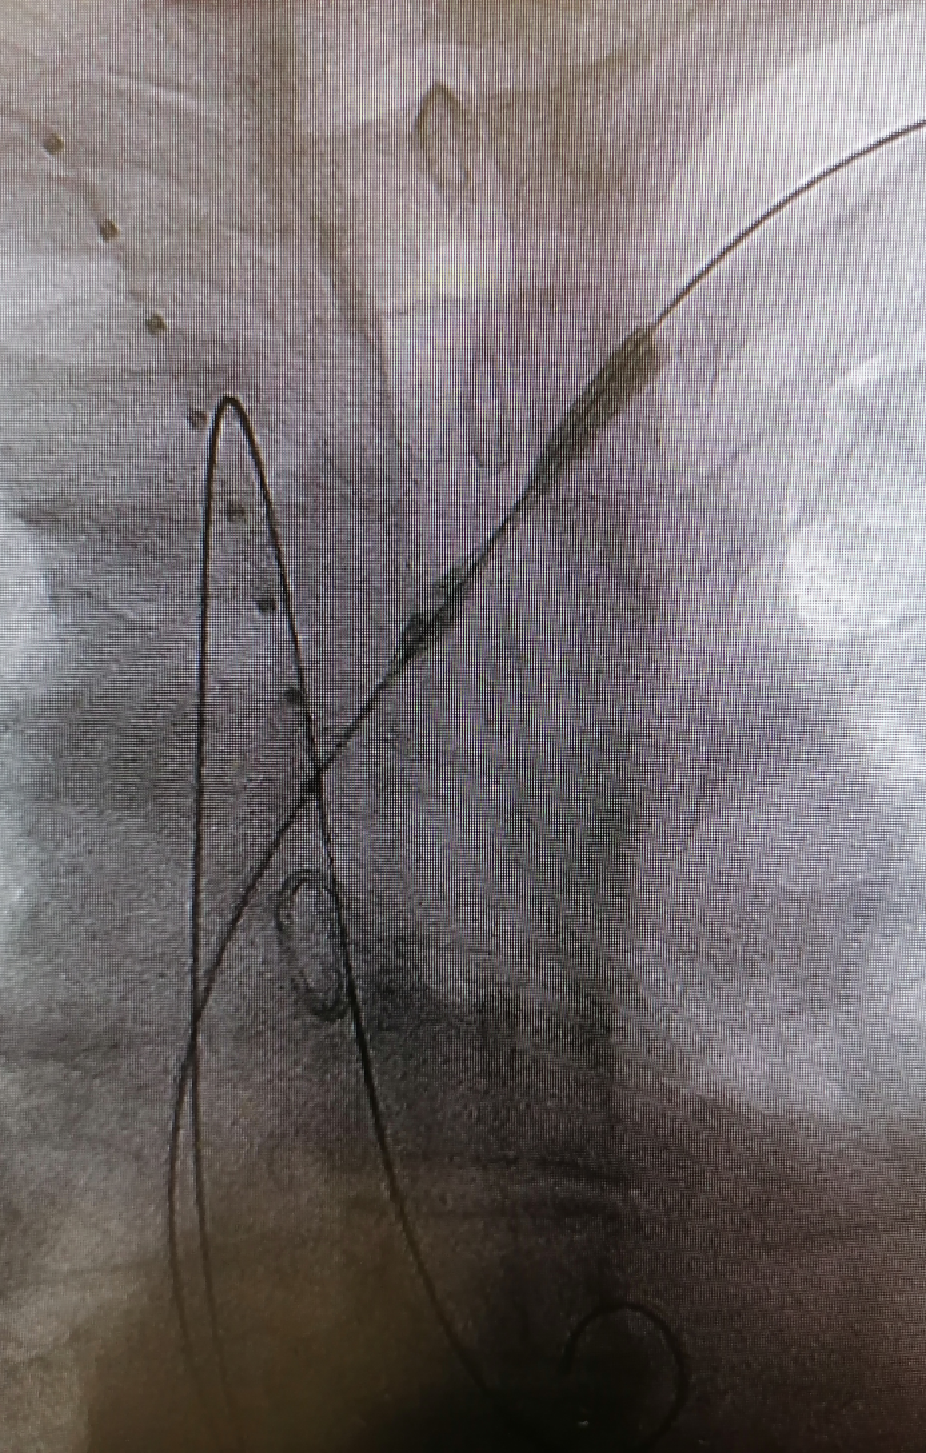

★Case 2 穿透性溃疡,右位弓

治疗难点:右位弓,锚定区不足、四分支走行变异,LSA重度狭窄

治疗目的:重塑主动脉形态,保障弓上四支变异分支血管正常供血

手术策略:TEVAR+烟囱(右锁骨下动脉)+潜望镜(左锁骨下动脉)

结果:四支血管血运恢复,术后造影血流通畅

释放主体支架

建立左锁骨下轨道

建立潜望镜